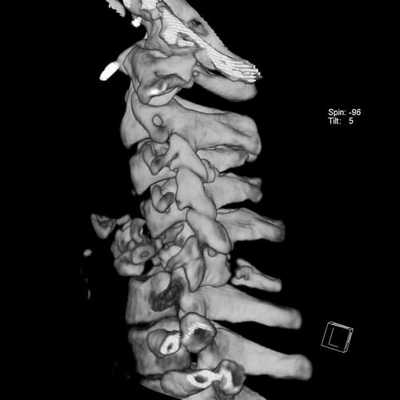

КТ, в отличие от МРТ позвоночника, проводится с помощью небольшого количества рентгеновского излучения. По сути дела, компьютерный томограф - это улучшенный рентгеновский аппарат, позволяющий делать объемные снимки и рассматривать отдельные срезы исследуемой области. КТ наиболее эффективна при диагностике повреждений костных структур и кровотечений. Кроме того, компьютерная томография используется для диагностики сложных травм позвоночника и обследования полых внутренних органов в случаях, когда МРТ провести невозможно.

Что КТ позвоночника покажет лучше, чем МРТ

КТ позвоночника - это приоритетный способ обследования позвонков. Ее следует выбрать, если у пациента:

- произошла травма позвоночника;

- есть перелом позвонков.

Травмы позвоночника включают в себя обширный перечень патологий: ушибы, дистрофии (надрывы или разрывы связок и сумок суставов позвонков без смещения), переломы остистых, поперечных отростков, переломы дуг и тел позвонков, подвывихи и вывихи, травматический спондилолистез. По самому механизму травмы врач уже может предположить, какой участок спины поврежден. Например, хлыстовые повреждения характерны при ДТП, когда происходит резкое сгибание. Также для такого типа нарушений функций позвоночника характерны падения с высоты, травмы ныряльщиков, производственные травмы.

Для точной классификации травмы позвоночника и оценки ее последствий врачу необходимо сделать КТ.

Компьютерная томография также является первичным методом диагностике в экстренных случаях, когда больной попадает по скорой в больницу. Дело в том, что в отличие от МРТ, которое требует 20 минут на исследование одного отдела позвоночника и почти часа для сканирования всей спины, КТ всего позвоночника можно сделать за 5-7 минут. Такая скоростная диагностика очень важна для пациентов в критическом статусе.